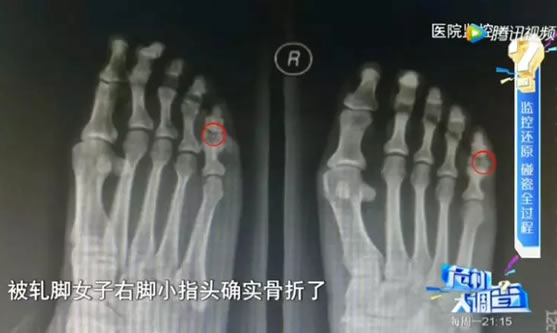

这名碰瓷女子也不是来假的

送往医院后发现脚趾确实骨折了

但事后经调查查明

她是事前用木槌砸断自己的脚趾!